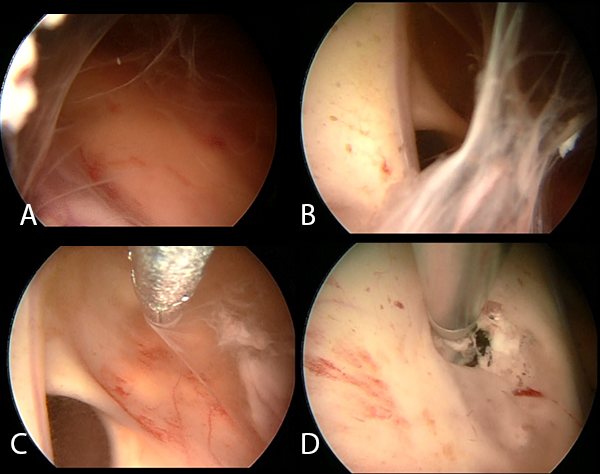

Se realizó la neuroendoscopía utilizando una óptica de 0 grados, de 30 cm. ingresando por el lóbulo frontal derecho. Inmediatamente al ingreso de la óptica se evidenciaron múltiples adherencias intra ventriculares. El foramen de Monro se encontraba parcialmente obstruido por una adherencia, además el epéndimo presentaba coloración amarillenta y las adherencias se encontraban difusamente en los ventrículos. Se intentó realizar una extracción de las membranas, pero se encontraban adheridas firmemente a las paredes ventriculares. (Imagen 4). Se realizó la fenestración del Septum Pellúcidum, con colocación de una nueva DVE, por lo que el paciente presentó mejoría clínica e imagenológica (Imagen 5).

Imagen 4: Fotografías intraoperatorias endoscópicas del ventrículo derecho. (A).Múltiples adherencias intraventriculares con epéndimo ligeramente amarillento. (B) Se evidencia obstrucción parcial del foramen de Monro. (C) Se realiza la extracción parcial de membranas intraventriculares. (D) Realización de la fenestración del Septum Pellucidum. Se evidencia ligero punteado en el epéndimo. SP: Septum Pellucidum; VSA: Vena septal anterior; FM: foramen de Monro; FO: fórnix.

Torrez-Corzo et al.(12) realizaron 24 endoscopías ventriculares a pacientes con meningitis, reportando que dichos pacientes presentaron aracnoiditis adhesiva, que incluso cubrían nervios craneales. Los hallazgos endoscópicos en nuestro paciente fueron similares, ya que se evidenciaron múltiples adherencias.